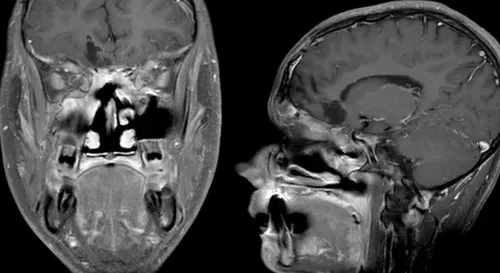

关键发现为:头颅影像学检查显示脑组织与鼻旁窦右侧存在5.5×4.4×5.6厘米的占位性病变。该肿瘤原发于鼻腔、筛窦和蝶窦区域,已侵蚀筛板结构进入前颅窝,导致额叶下部出现占位效应并引起轻微中线移位。脊柱MRI检查未见转移性病灶。

术后临床观察显示,患者神经系统状况未出现恶化,头痛症状在术后第十天显著减轻。术后48小时MRI检查证实肿瘤大体全切。后续治疗包括30次分割放疗,总剂量6000cGy,靶区覆盖肿瘤及周边边缘,同步实施顺铂化疗。